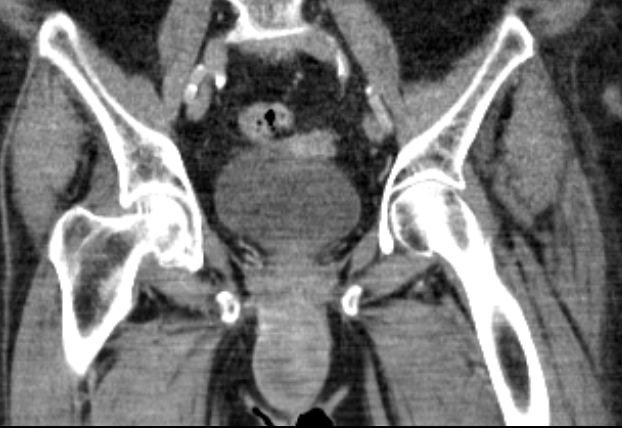

82-jährige Frau mit einem Leiomyosarkom der Vulva rechts pT2a N0 M0, V1, G2.

Klinik: Vulva-Tumor rechts. Der Tumor ist relativ glatt begrenzt und gut 5 cm groß; er ist auf dem absteigenden Schambeinast beweglich und reicht dicht bis an die Urethralöffnung heran.

8 Monate nach Primärtherapie auftreten von Knochenmetastasen. Kein lokales Rezidiv.